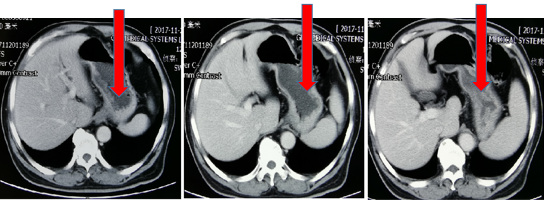

CT(外院2018.05):肝内多发占位,考虑转移;贲门胃底部溃疡性肿物;胃低及胃左动脉多发肿大淋巴结;考虑转移。

图表1-2:CT(外院2018.05)